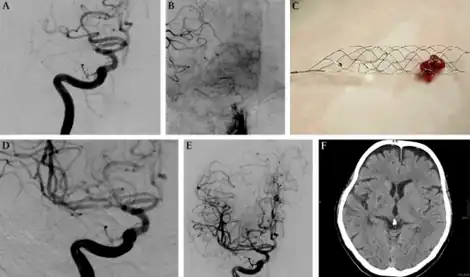

| Mechanical thrombectomy using a Solitaire stent-a)Injection of internal carotid artery shows embolic occlusion b)leptomeningeal collaterals visualized c)solitaire stent loaded with thrombus d,e)DSA with injection of right ICA f) 22 months after there is a small post-ischemic scar | |

Mechanical thrombectomy, or simply thrombectomy, is the interventional procedure of removing a blood clot (thrombus) from a blood vessel. It is commonly performed in the cerebral arteries (interventional neuroradiology). The effectiveness of thrombectomy was confirmed in several randomised clinical trials conducted at University at Buffalo and elsewhere by a team of researchers including Elad Levy.[1]